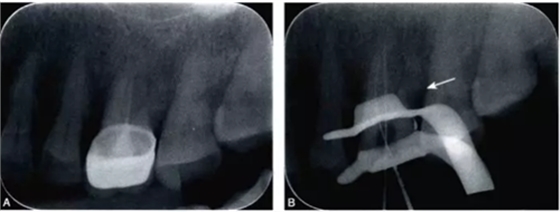

完全鈣化根管在X線片上的表現(xiàn)是根管影像模糊,密度增高,根管密度與周圍的牙本質(zhì)密度接近,甚至無法區(qū)分根管與牙本質(zhì)的影像。有些根管,可表現(xiàn)為根管影像時(shí)斷時(shí)續(xù)或模糊不清,為不完全鈣化根管表現(xiàn)(圖4-1A)。細(xì)小根管的病例在X線片上,根管影像隱約可見,與同名牙或鄰牙相比,根管較為細(xì)小影像清晰度降低。

細(xì)小鈣化根管的根管口,即使是在口腔手術(shù)顯微鏡下,也不容易被發(fā)現(xiàn)。在鈣化根管的早期,鈣化牙本質(zhì)的顏色可能與周圍正常牙本質(zhì)不同,因此,多數(shù)情況下,利用口腔手術(shù)顯微鏡能夠發(fā)現(xiàn)根管所在位置。有的鈣化根管牙本質(zhì)與周圍牙本質(zhì)顏色相似,難以區(qū)分,此時(shí)借助手術(shù)顯微鏡的高倍放大作用,結(jié)合根管解剖知識,仔細(xì)觀察顏色的細(xì)微差異,有助于提高探查根管口的成功率。完全鈣化的根管,表現(xiàn)為均質(zhì)的硬組織結(jié)構(gòu),有時(shí)與正常牙本質(zhì)結(jié)構(gòu)難以區(qū)別,當(dāng)采用各種方法均無法疏通時(shí),為了避免產(chǎn)生新的并發(fā)癥,不宜強(qiáng)行疏通,可定期追蹤觀察(圖4-2)